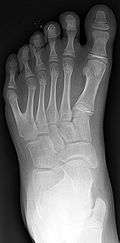

Classification is performed by using x-ray imaging to see the bone structures.[15]